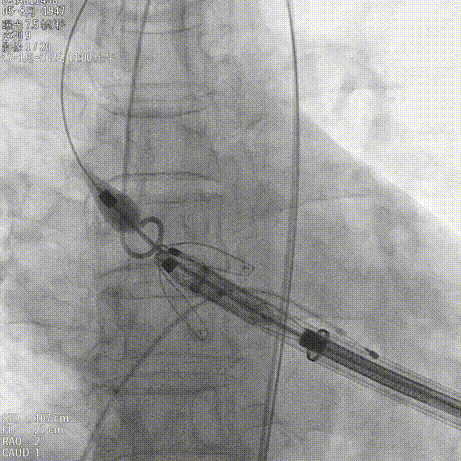

造影确认右窦居中位置

释放定位件入窦

造影确认定位件入窦

调整轴向再次造影确认定位件入窦